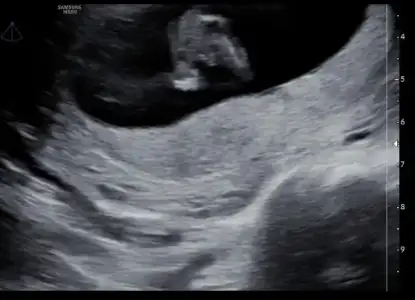

Merhabaaaa , 12. Haftada erkek dedi ama beni hep hissim kızdıı en önemlis sağlıklı olması tabiki ama ama içim içimi yiyiyor doktor emin ama ben emin olamıyorum :) bi bakabilirmisiniz böyle birşey yaşayan varmı?

8D8B5252-A5B6-48D2-B9F4-F1DB57A8A20D.webp

633BD55A-1707-4AEB-9744-8E18CB5E9F3B.webp

0F34E68A-5766-4A2F-8A9C-A0E5C7DF57A7.webp

8D8B5252-A5B6-48D2-B9F4-F1DB57A8A20D.webp 633BD55A-1707-4AEB-9744-8E18CB5E9F3B.webp 0F34E68A-5766-4A2F-8A9C-A0E5C7DF57A7.webp